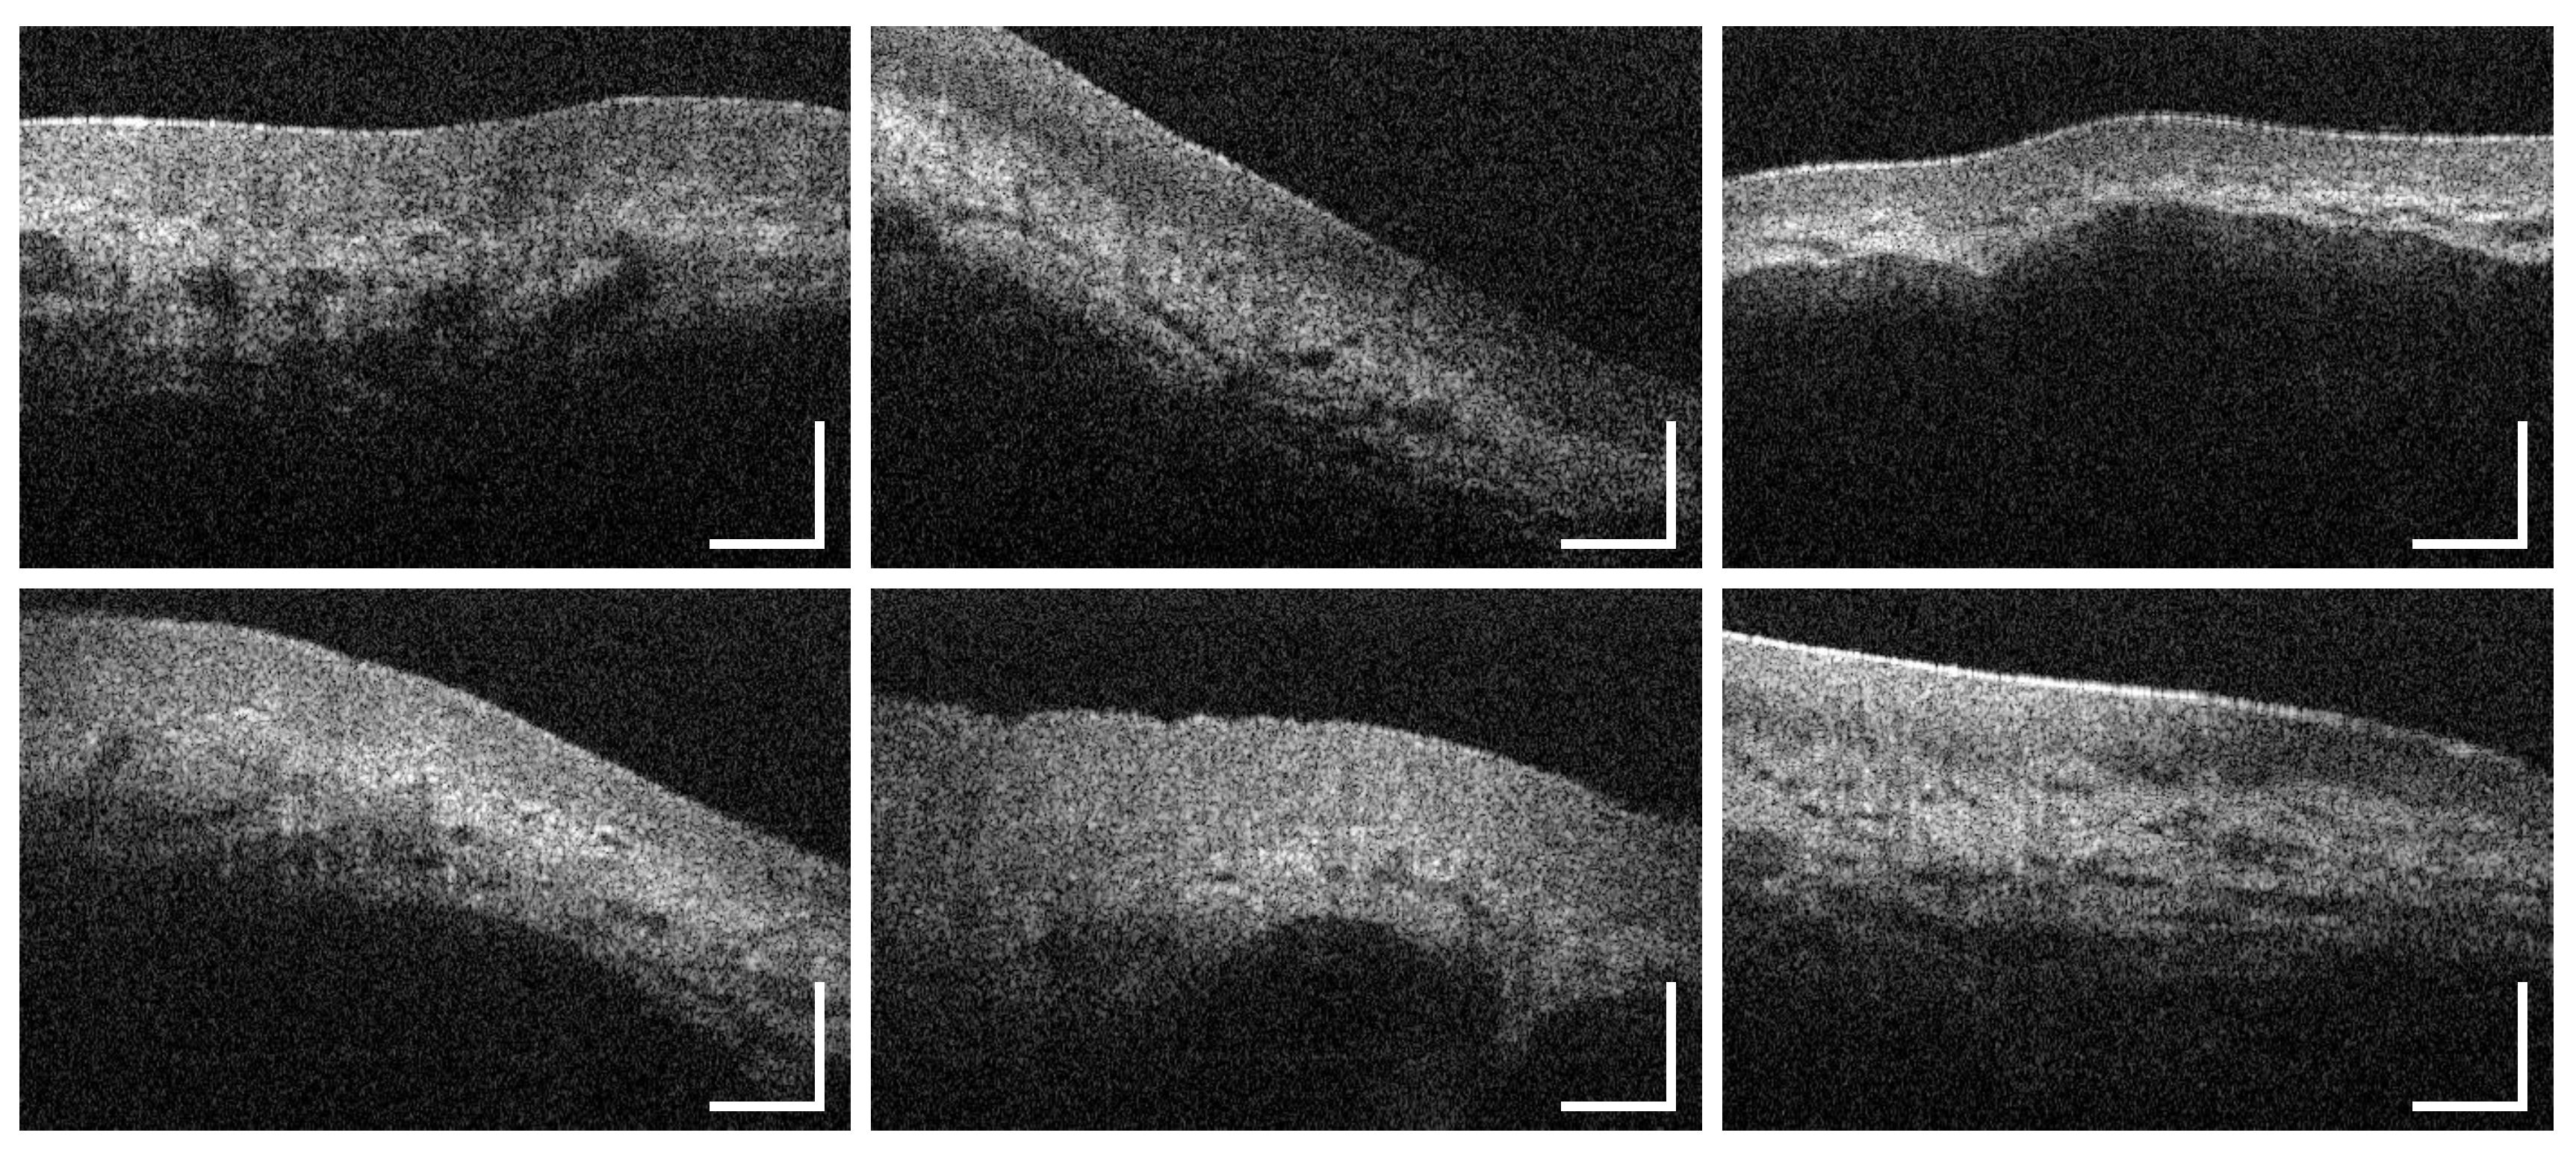

3.1. Labial and Alveolar Mucosa

3.2. Buccal Mucosa

3.3. Sublingual Mucosa

3.4. Hard Palate

3.5. Soft Palate and Oropharynx

3.6. Palatine Tonsils